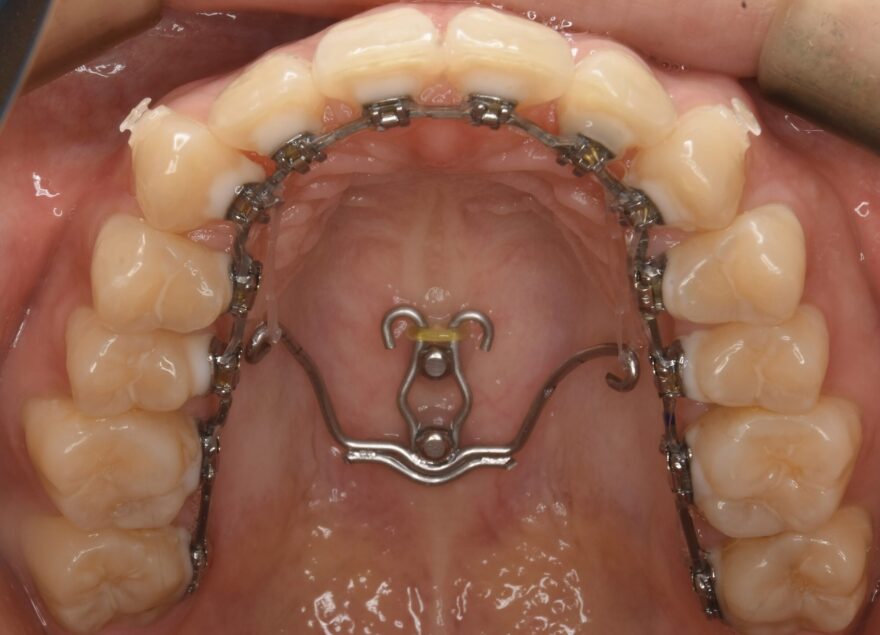

治療中の口腔内写真

上顎は裏側に矯正装置が付いています。

口蓋に2本の歯科矯正用アンカースクリューが埋め込まれ、裏側の矯正装置とゴムで繋がっていることがわかります。